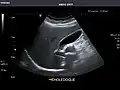

Abdominal Ultrasound (Full Exam)

STRUCTURED REPORT

(Technique: Transabdominal ultrasonography; Device: Toshiba Aplio XG)

Kidneys: Right and left kidneys measure 11.5 cm and 12 cm in length respectively. No hydronephrosis. Small left lower pole kidney cyst.

Right kidney -